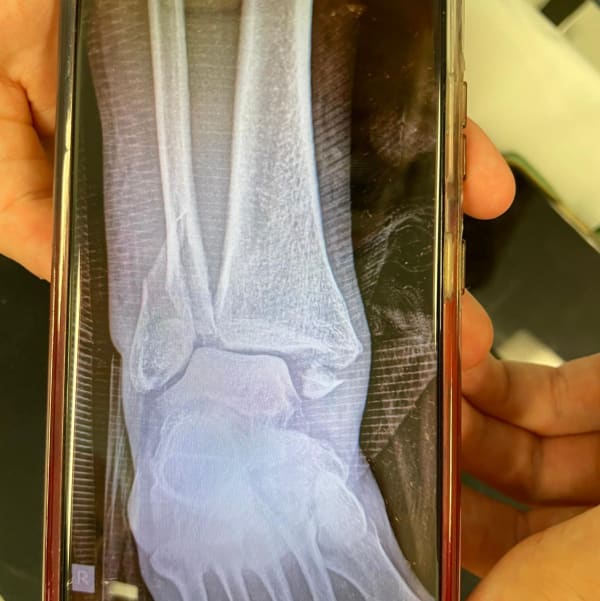

Fiona Taylor On the evening of the 7th April I fell bouldering. Originally we believed this was just a dislocation that would be fixed quickly as I was not in much pain but the paramedics made it obvious it was likely much worse getting me quickly on morphine and strapping me up. The X-rays in the emergency department confirmed their suspicions, I had broken my ankle and not to do things half arsed I had in fact dislocated my ankle and fractured all three bones - a trimalleolar or trifecta as I like to call it. In the ED they attempted to manoeuvre my foot back into place as best they could before the first plastering. Apparently I would be sedated and therefore be semi awake, feel no pain and likely not remember any of it. At this point I still wasn’t experiencing pain, more like an ache unless it was bumped or moved. I felt nothing as they performed this resetting but I was fully conscious and chatting to them throughout the process. Having only had 15 mg of morphine when the paramedics first arrived and a few sucks on a green whistle they were all rather surprised my pain hadn’t increased once the shock and adrenaline wore off, perhaps Us London folk are just raised tougher! A lack of beds on orthopaedics meant I slept the first hour that night in the plaster room and then was moved to a a neuroscience ward about 4am and was nil by mouth expecting an operation the following day.

Fiona Taylor After waiting nil by mouth for surgery again the surgeon finally came to meet me and take a look and talk through the surgery. It’s not gonna be a simple surgery, screws plates and likely 3 incisions, one on each side and one up the back from heel to calf, they’d need to see the state of the tendons and ligament once they open it up. A plate may also be needed at the front which would likely mean a second op later to remove it. Unfortunately on removing the bandages and opening the front of the cast he advised I’m still too swollen and will be sent home until the swelling has gone down enough to operate. I’m to return on Monday ( 3 days later) to see if it’s reduced enough to schedule the surgery. Leave on crutches for a weekend of rest at home